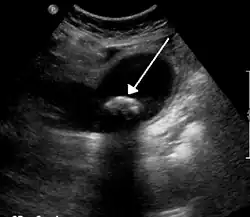

La colique hépatique est souvent liée à des calculs biliaires

Une colique hépatique (une douleur qui n'a rien de colique et rien d'hépatique, le nom plus approprié étant "douleur vésiculaire") est un symptôme douloureux ressenti par un patient dans la partie supérieure droite de l'abdomen. Cette douleur est généralement isolée ; elle ne s'accompagne pas de fièvre, d'altération de l'état général ou d'ictère. Elle peut s'accompagner d'une fièvre et d'un ictère dans la triade de charcot ou de villard. C'est une douleur généralement déclenchée par un repas riche en graisse (entrainant une augmentation de la CCK --> contraction vésicule biliaire).

On retrouve ce symptôme, par exemple, lors de l'expulsion d'un calcul hors de la vésicule biliaire (en même temps que la bile), lors de la contraction de celle-ci. Le calcul provoque une douleur vive en se déplaçant dans les voies biliaires : cette douleur peut irradier jusqu'aux côtes et l'épaule du côté droit.